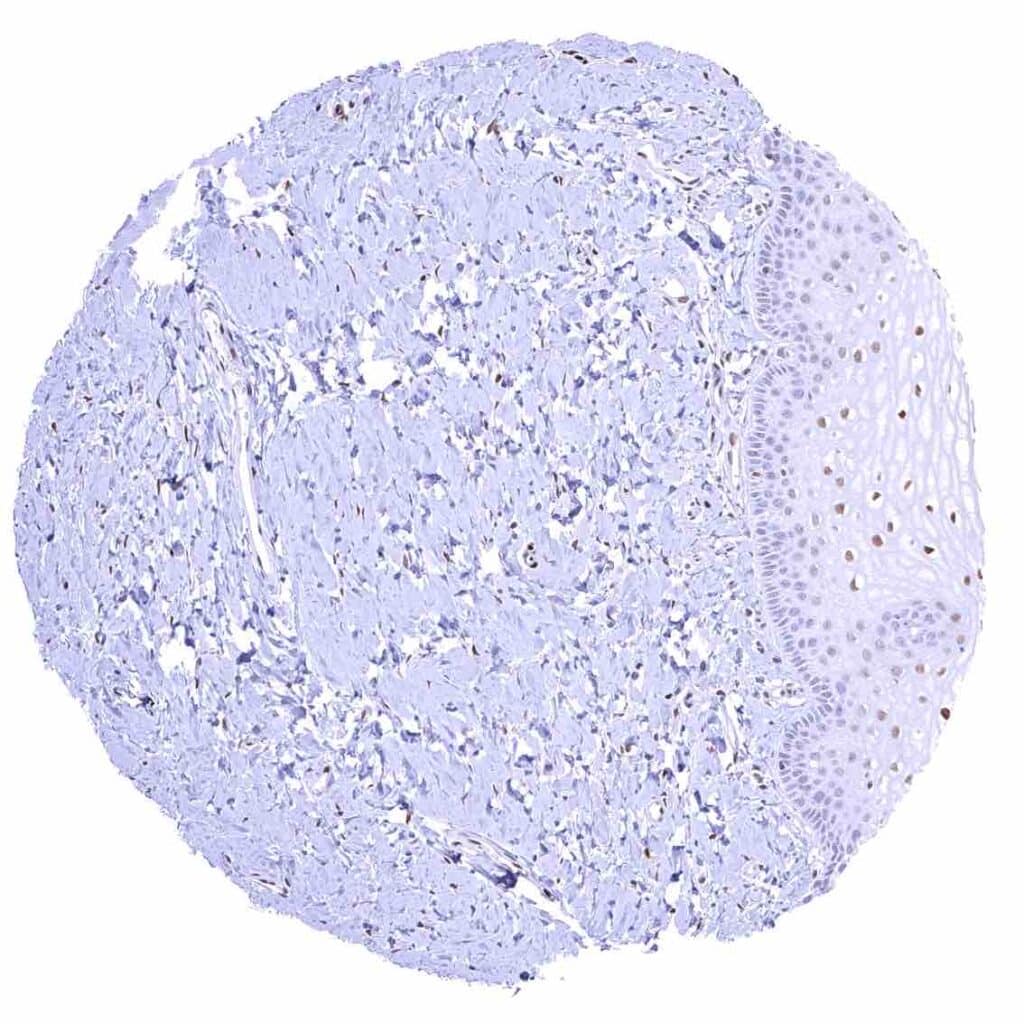

Prostate